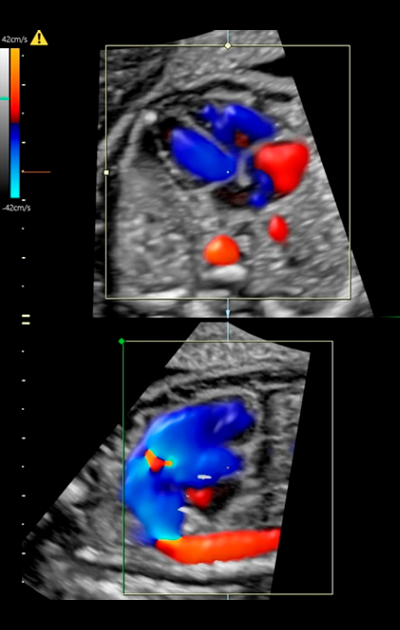

ExamesUltrasom 2D | 3D e 4DUltrassom Doppler ColoridoEcocardiografía FetalCálculo de risco S.Down.